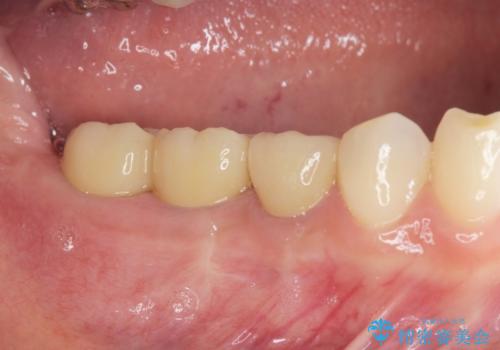

自然な色調のクラウンが製作され、審美障害が改善し喜んでいただくことができました。